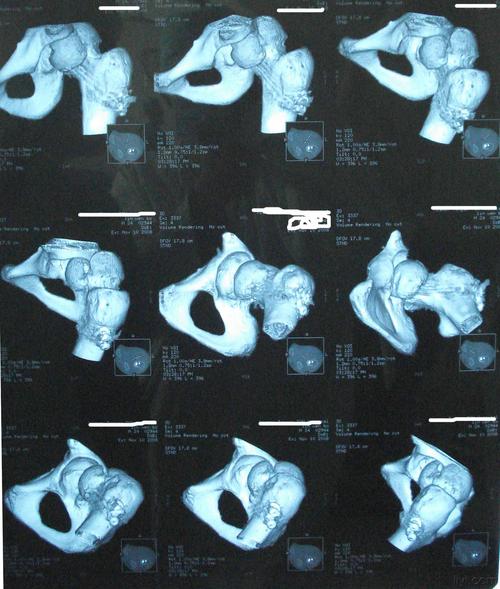

双髋关节ct示:左股骨颈骨折

ct:股骨颈骨折头下型

股骨颈骨折 or 股骨头骨折